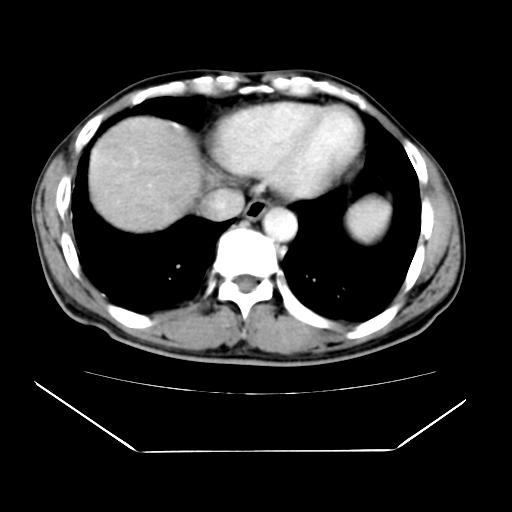

男性,55岁,外院体检afp明显升高,但b超未发现异常,否认乙肝病史。来我院ct增强。有延时扫描。

肝脏右叶动脉期可见低密度影,至延迟期被充填,考虑血管瘤可能性大。

标题: 肝右叶病灶强化

肝右叶病灶

不排除肝右叶肝癌可能。

这个不是肝右静脉吗,这么大的病灶b超不可能发现不了吧

如果这个是癌灶的话则下腔静脉有瘤栓可能

肝6段血管瘤

血管瘤可能性大。

考虑肝右静脉影。